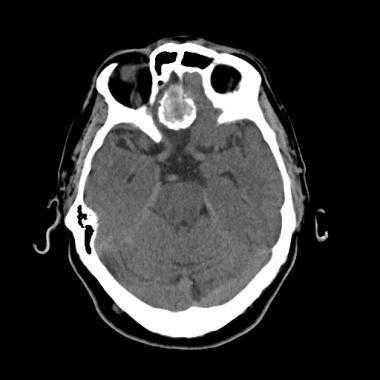

КТ при менингиоме

Компьютерная томография (КТ) часто используется для оценки опухолей мозга. Обычно на изображении без контрастного усиления она представлена в виде четко очерченного внемозгового (экстрааксиального) образования с ровными краями, прилегающего к твердой мозговой оболочке. Примерно 70-75% обладают повышенной плотностью по сравнению с окружающей их паренхимой головного мозга, а около 25% — изоденсивны. Редкая группа опухолей (липобластный подтип) содержат включения жира и, таким образом, характеризуются пониженной рентгеновской плотностью.

Кальцинаты являются другой частой находкой; их обнаруживают в 20-25% случаев. Кальцинаты на КТ могут быть узловыми, точечными или сплошными плотными. Часто наблюдается вазогенный паренхиматозный отек окружающей мозговойо ткани, визуализирующийся на снимке как участок паренхимы пониженной плотности. В некоторых случаях отек настолько выражен, что, ввиду преимущественного поражения белого вещества, может выглядеть в виде пальцевидных зон низкой плотности. Впрочем, отек отсутствует примерно в 50% случаев вследствие медленного роста опухоли.

Внутривенное введение контраста помогает в оценке менингиомы: в более 90% случаев наблюдается интенсивное равномерное повышение плотности после введения контраста.

Неоднородный характер контрастирования может быть следствием некроза или, реже, кровоизлияния.

З адняя тенториальная менингиома на корональном КТ-изображении с контрастным усилением. К намету мозжечка прилежит объемное образование повышенной плотности с четкими краями. Визуализируются застой спинно-мозговой жидкости, легкий отек прилежащих тканей, гомогенный характер контрастирования, а также расширение желудочков.

Примерно 90% менингиом видны на КТ-изображениях. Основная роль КТ, по сравнению с МРТ, заключается в отображении изменений в подлежащих костях и наличия кальцинатов в опухоли.